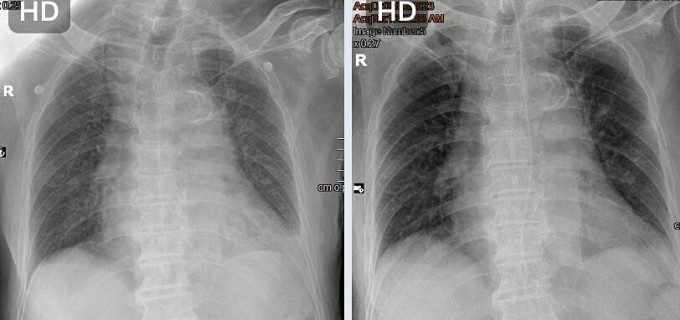

Theo kết quả chụp X-quang phổi vào ngày 8/6, phổi mờ trắng do nhiễm Covid-19. Hình ảnh MRI 3 Tesla ghi nhận bệnh nhân bị đột quỵ não nhẹ nhưng đã qua giờ “vàng”, mạch máu yếu và xơ vữa. Người bệnh còn có nhiều bệnh nền nguy hiểm như rung nhĩ, suy tim, tăng huyết áp, tiểu đường type 2.

Hình ảnh X-quang phổi trắng mờ do nhiễm Covid (trái) và sau điều trị phổi đã rõ ràng hơn (phải) (Nguồn: Bệnh viện Đa khoa Tâm Anh)

Mỗi ngày các bác sĩ thăm khám nhiều lần, có chế độ dinh dưỡng phù hợp, ổn định chỉ số huyết áp, đường huyết… Người bệnh được bổ sung thêm thuốc an thần và theo dõi sát sao. Bệnh nhân ổn định từ từ, phổi hồi phục dần, ngưng thuốc điều trị tâm thần kinh, tỉnh táo và phản xạ nuốt tốt hơn.